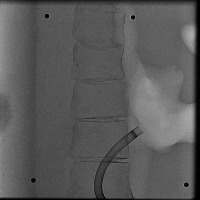

Healthcare Monitoring: "Cath" can be used in a real-time monitoring system within healthcare facilities. It can identify the position and type of a catheter tip in an x-ray, greatly helping healthcare professionals to assess the situation of patients having a lumbar puncture or spinal catheter implantation.

Medical Diagnosis: "Cath" can be used in the diagnosis of possible complications associated with catheter placements. Early detection of catheter displacement can prevent further complications.